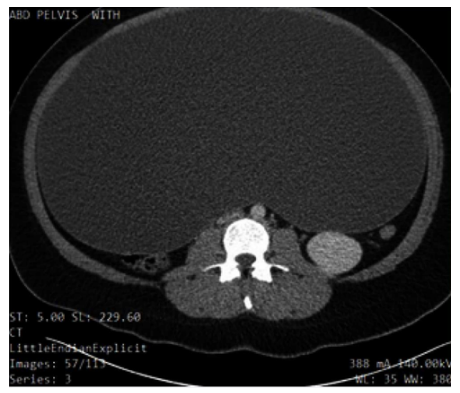

On examination, the patient appeared to be obese, welldeveloped, anxious, and cooperative. She was not able to tolerate a speculum examination due to the pain. There was no pulsatile abdominal mass, guarding of the abdomen, nor any generalized and/or rebound tenderness or rigidity. The lower left quadrant of the patient’s abdomen was tender with mild distention and normal bowel sounds were heard. An elevated blood pressure on admission (145/89) was noted. The urinalysis was unremarkable. Blood analysis showed hypochromic, microcytic anemia (10.3 g/ dL) with +1 anisocytosis (generally associated with iron deficiency anemia [11], and mild elevated chloride (109 mEq/L) and elevated glucose (109 mg/dL) levels. A pelvic ultrasound reported a normal uterus with no endometrial abnormalities, and the right ovary appeared normal. The left ovary was not visualized (Figures 1 and Figure 2). A large cystic structure was seen, whose origin was unknown. An abdominal/pelvic computerized tomography (CT) with contrast found a 36 cm cyst lesion filling the abdominal and pelvic cavity which appeared to originate from the left adnexa with a complicated hyperdense fluid or debris focus noted in the inferior margin of the cyst (Figure 3). The surrounding structures appeared unremarkable. There was a trace amount of fluid in the Pouch of Douglas. (Figure 4).

Figure 4: Coronal slice of non-contrast CT of abdomen demonstrating the compression of the neighboring structures up to the thoracic cavity, which explains some of the patient’s symptoms, such as shortness of breath.